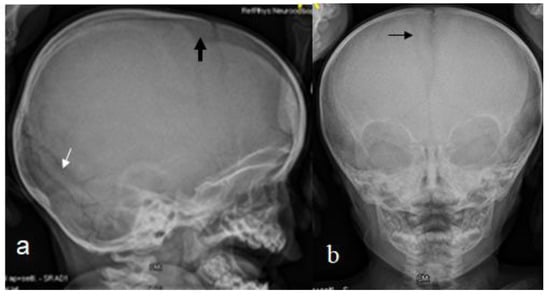

The 14-months-old boy was referred to our consultation for a clinical assessment and diagnosis. The clinical examination revealed a growth deficiency of -2SD, pseudo-hydrocephalus with a prominent forehead, deep seated eyes and sparse hair. Down slanting palpebral fissures, a beaked nose with a protruding nasal septum below the hypoplastic nares, low set ears and thin lips were notable features. The thin upper lip was associated with retrognathia. The limbs were short, the thumbs were relatively short and wide, the hallux was wide and the rest of the digits of the hands and feet were short. Relative hemi-hypertrophy could be elicited. The hands were with relative camptodactyly. A musculoskeletal examination showed moderate ligamentous hyperlaxity. The intellectual performance was difficult to assess, though his smile was somehow associated with peculiar facial expressions overwhelmed by a bizarre facial grimacing when trying to smile. The skeletal survey and lateral skull radiograph showed a very large anterior fontanelle (massive defective ossification) associated with frontal bossing, giving the impression of pseudo-hydrocephalus. There were also hyperostosis of the skull base and Wormian bones along the lambdoid sutures (Figure 4a). An AP skull radiograph showed the frontal bossing and the persistence of the anterior fontanelle (Figure 4b). Genetic testing was not performed for this patient. A 2-year-old boy presented with the phenotype and genotype of RSS. He underwent a 3D reconstruction CT scan to assess the anatomy of the skull and the anterior fontanelle. A 3D reconstruction CT scan of the skull (anterior view) of the 2-year-old boy showed frontal bossing and the persistent open anterior fontanelle (Figure 5a). A 3D reconstruction of the crown of the skull of the same boy showed a defective ossification of the anterior fontanelle and a defective and disorganized ossification of the skull bones (arrows) (Figure 5b). Hypomethylation of the imprinting control region (ICR1) on chromosome 11p15 and maternal uniparental disomy of chromosome 7 was encountered.

Figure 4. Lateral skull radiograph of a 14-month-old boy with RSS showed a very large anterior fontanelle (massive defective ossification) associated with frontal bossing, giving the impression of pseudo-hydrocephalus-arrow hyperostosis of the skull base and Wormian bones along the lambdoid sutures (a). AP skull radiograph showed the frontal bossing and the persistence of the anterior fontanelle-arrow (b).